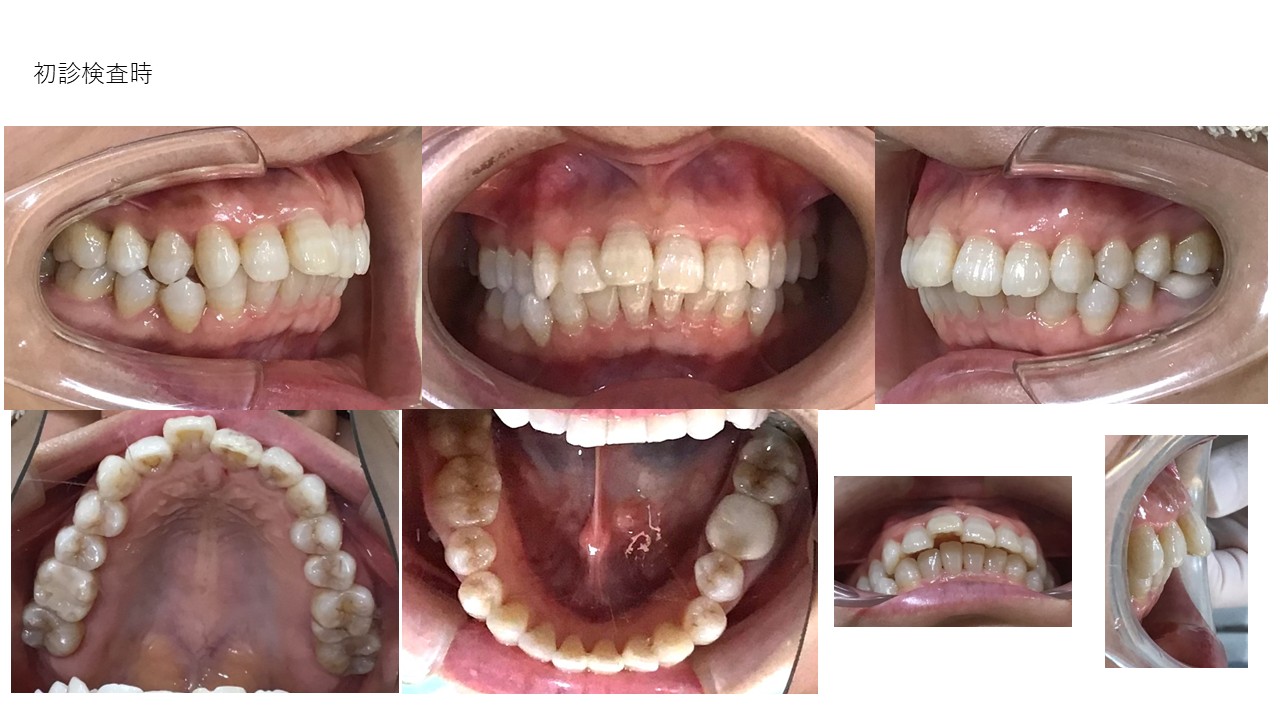

裏側ワイヤー矯正

| 主訴 | 叢生、前突 |

|---|---|

| 年齢 | 30代 |

| 治療期間 | 1年(継続中) |

| 治療回数 | 12回 |

| 治療に用いた主な装置 | カスタムメイド型リンガルブラケットデジタル矯正装置(WIN) |

| 治療費 | 1,300,000円(税別) |

| リスク・副作用 |

1. 矯正装置を装着すると、不快感や痛みが生じることがあります。通常、数日〜1週間ほどで痛みが消失し、慣れることが多いです。 2. 歯の動き方には個人差があり、予想された治療期間より長引く可能性があります。 |